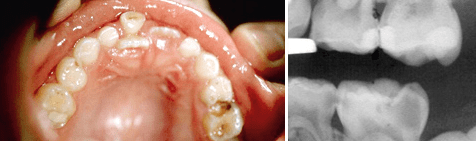

Die Unterschiede zwischen Milchzähnen und permanenten Zähnen hinsichtlich ihrer Anatomie, Morphologie und Physiologie sind doch so groß, dass sich daraus prinzipielle Unterschiede für die Durchführung endodontischer Maßnahmen ergeben. Zunächst weisen Schmelz und Dentin bei Milchzähnen wesentlich geringere Wandstärken auf. Diese banal erscheinende Feststellung hat zur Folge, dass gerade im Bereich der Approximalräume von Milchmolaren, aber auch an den Glattflächen der Frontzähne, wo die Wandstärken besonders gering sind, die Pulpa bei Kariesdefekten bereits häufig mitbeteiligt ist (Abb. 1). Hinzu kommt eine geringere Reaktionsfähigkeit der Milchzahnpulpa auf äußere Reize, was dazu führt, dass die entzündete Pulpa nicht mit Schmerzsensationen reagiert und der tatsächliche Pulpazustand sowohl für das Kind/die Eltern als auch für den Zahnarzt im Verborgenen bleibt. Dieser primär-chronische Entzündungsverlauf findet sich im Milchgebiss nicht nur bei Pulpaerkrankungen häufig, sondern auch bei den apikalen Parodontitiden, die oft als Folgezustände früherer akuter oder chronischer Pulpitiden entstehen. Die physiologische Resorption der Milchzähne im Zuge des Zahnwechsels mit abnehmender Reparationsfähigkeit der Pulpa, die große Variationsbreite der Milchmolarenwurzeln sowie deren starke Krümmung (um die Keime der permanenten Nachfolger herum) sind weitere wichtige Besonderheiten, die bei der Anwendung endodontischer Verfahren im Milchgebiss zu berücksichtigen sind.

Abb. 1 Approximalkaries an Milchmolaren.